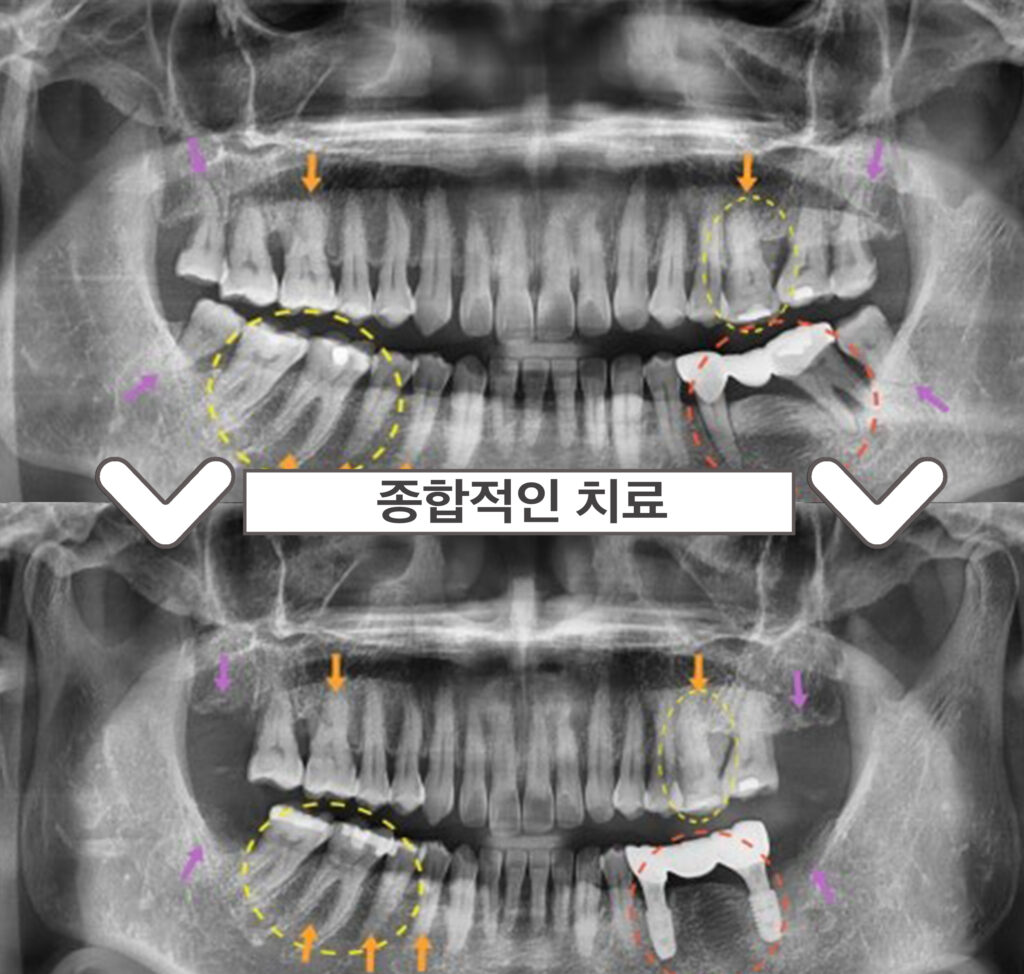

정밀한 검사를 위해

파노라마 사진을 촬영해 보았더니,

제일 불편감을 호소하셨던

빨간 동그라미 표시의

왼쪽 아래 어금니(#35,37) 부위는

기존 브릿지 보철물이

수복 되어 있는 상태였습니다.

보철물 주변 잇몸뼈가

많이 흡수되어 있는 상태로

동요도가 2도 이상으로 많이 흔들려

안타깝게도 살려 쓰기에는 힘든 상황이라

발치 후 임플란트 식립을 계획하였습니다.

또한 보라색 화살표 부위의

사랑니가 4개 모두

맹출이 되어 있었는데요.

사랑니가 맨 안쪽에 위치해 있다 보니

위생관리가 잘되지 않고 있어

추후 다른 치아에까지

영향을 끼칠 것을 고려하여

사랑니 모두 발치를 진행하기로 하였습니다.

그리고 환.자분께서 내원 당시

찬물에 치아가

많이 시리다고 말씀해 주셨는데요.

확인해 보았더니 주황색 화살표 부위의

치아 허리 부분에 해당하는

치경부가 많이 닳아 있는

치경부마모증이 있었습니다.

노란색 동그라미 표시의 치아들엔

우식이 발견되었는데요.

왼쪽 위 첫 번째 큰 어금니(#26)와

오른쪽 아래 큰 어금니 두 개(#46,47)는

기존 아말감 파절로

기존 충전물이 일부 파절되면서

주변으로 2차 우식이 관찰되었습니다.

또한 오른쪽 아래 두 번째 작은 어금니(#45)는

치.아 원심면에 우식이 보였습니다.